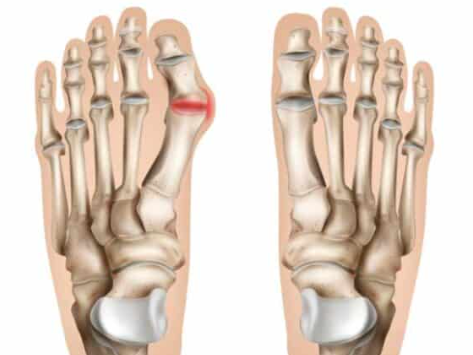

무지외반증("hallux valgus”)이란?

무지외반증은 발가락 통증을 일으킬 수 있는 특정한 상태입니다. 이는 발가락으로 통증을 유발할 수 있는 신경 주위의 조직이 두껍고 확장되는 경우 발생합니다. 이는 특히 세 번째와 네 번째 발가락 사이의 발의 앞부분에서 심한 불편함을 초래할 수 있습니다.

무지외반증의 증상

무지외반증의 흔한 증상은 다음과 같습니다.

- 발 앞부분에서 날카로운, 화끈한 통증.

- 영향을 받는 발가락에서의 저림 또는 따끔거림.

- 신발 안에 돌 또는 물체가 있다는 느낌.